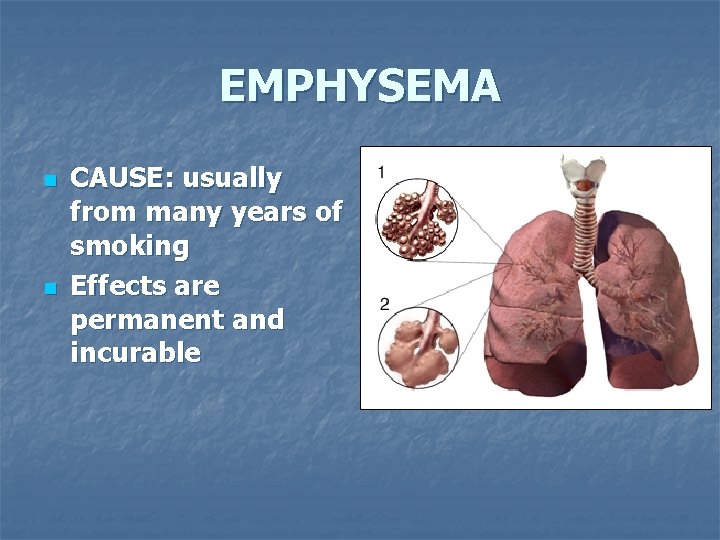

EMPHYSEMA n n CAUSE: usually from many years of smoking Effects are permanent and incurable